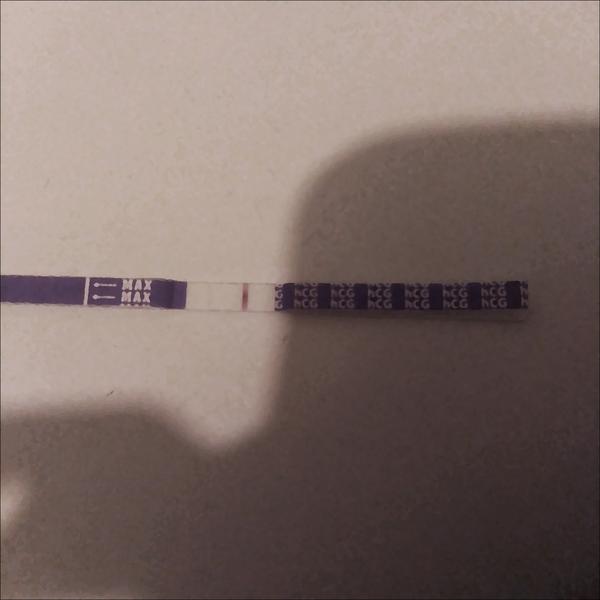

bola som u svojho gynekológa a spravil mi ultrazvuk. Vraj si nie je istý, či som tehotná, alebo mám zrazeninu. V krvi mám negatívny výsledok, ale test mi stále ukazuje pozitívny výsledok. Testy sú robené od 22.10 každý tretí deň.

Posledný piaty test bol robený 2.11.2019.